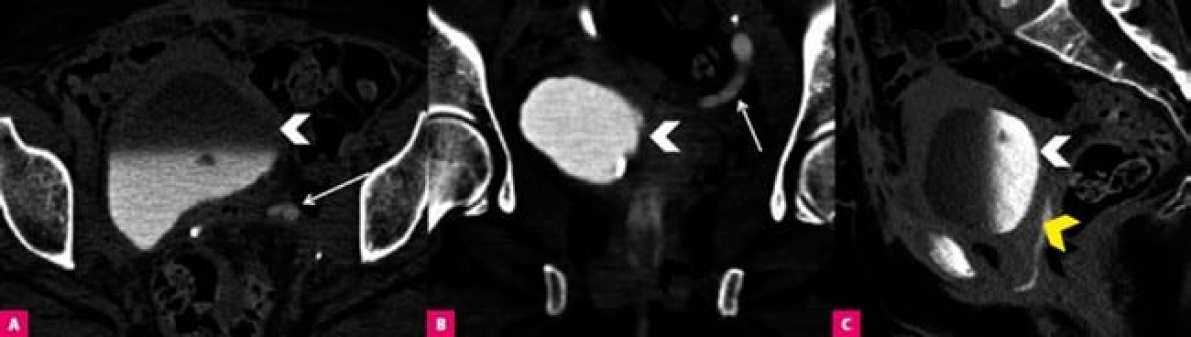

Обструкция кишечника у женщины после лапароскопической резекции кисты эндометрия яичника. A и B. Горизонтальный газ-жидкость в расширенных петлях тонкой кишки (звезды) и грыжа, образованная в разрезе (стрелка), визуализируемая на КТ-изображениях в осевой и фронтальной плоскостях.

Уретеро-вагинальный свищ у женщины после операции по поводу рака шейки матки. КТ-изображения в осевой (A), фронтальной (B) и сагиттальной (C) плоскостях показывают контрастную мочу в мочевом пузыре (белая стрелка) и заполненную контрастом полость между мочеточником и влагалищем (желтая стрелка), вкупе с расширением левого мочеточника (стрелка)